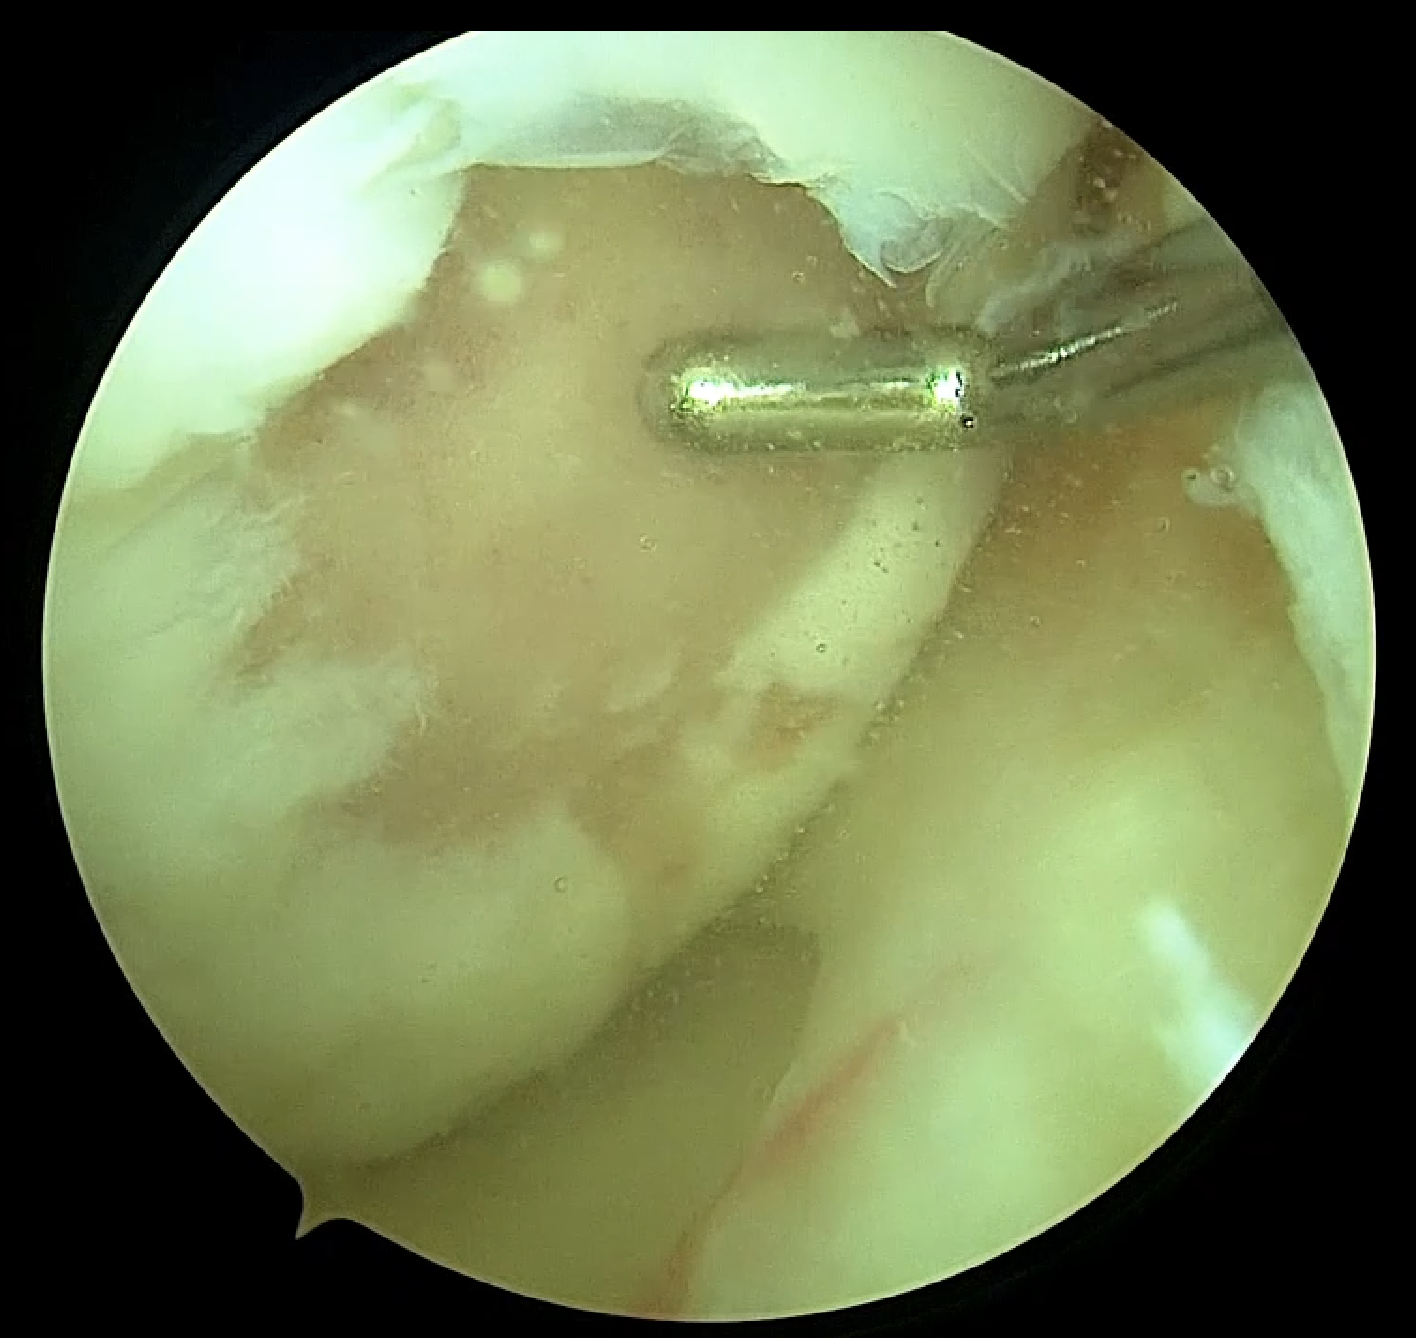

El origen de las lesiones del cartílago o lesiones osteocondrales es muy variado, pudiendo ser traumático o debido a enfermedades como la osteocondritis disecante que habitualmente generan lesiones aisladas o bien como resultado de procesos degenerativos que provocan un daño generalizado y derivarán en lo que conocemos como artrosis.

El tratamiento de la lesión osteocondral continúa siendo un reto hoy en día y dependerá de distintos factores como si se aborda en el momento agudo o no, si afecta únicamente al cartílago o también al hueso subcondral, del tamaño de la lesión y de las características anatómicas y antecedentes de cada paciente.